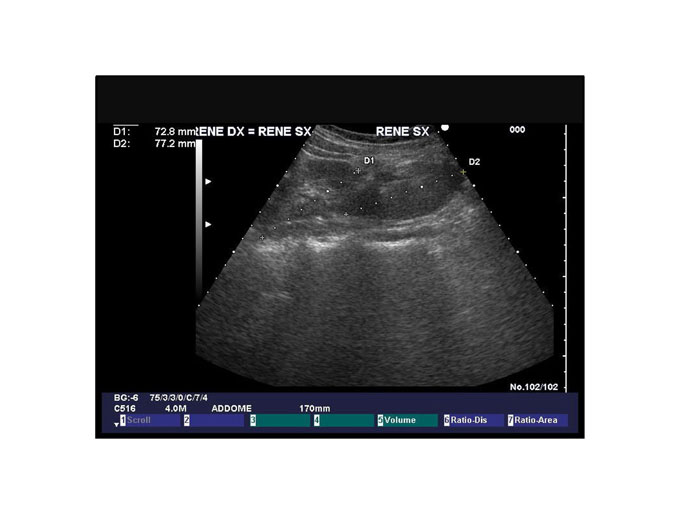

564_Foto-Poster[2]